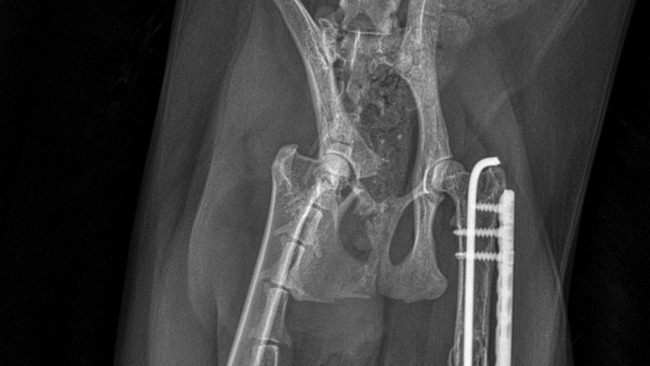

Kira w wypadku rozcięła udo na całej długości, a złamaniom uległy dwa żebra, skrzydło kości krzyżowej stawu krzyżowo-biodrowego prawego oraz doszło do złamania przezpanewkowego prawego stawu biodrowego ze zwężeniem kanału miednicy – bez kosztownej operacji Kira nie tylko nie wróci do pełnej sprawności, ale będzie też ogromnie cierpieć. :( Przez to nie będzie mogła znowu chodzić. Ponadto na zdjęciach RTG okazało się, że Kira niestety już przebyła operację wstawienia stabilizacji lewej nogi po złamaniu kości biodrowej – którą również będzie trzeba za jakiś czas usunąć, aby zapewnić jej komfort w poruszaniu się.